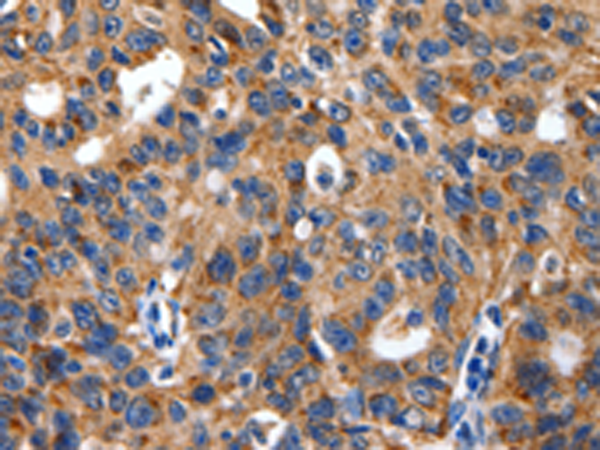

分类: 科研抗体货号: P10832别名: ALK-SMase应用: IHC反应种属: Human, Rat